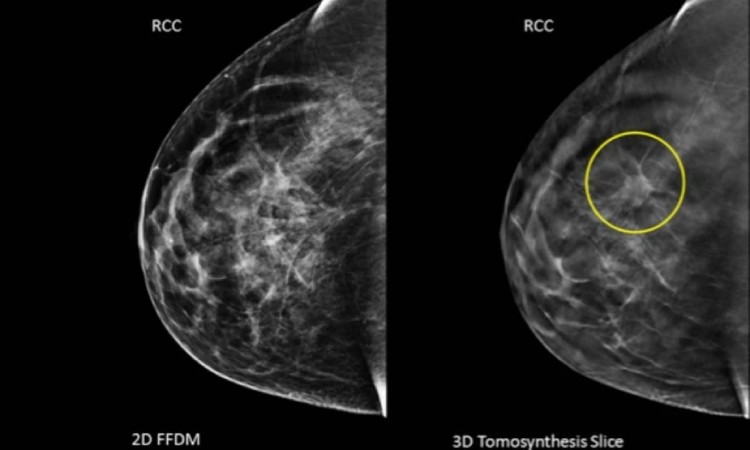

Mamografia

Exame radiológico das mamas, fundamental para a detecção precoce do câncer de mama, permitindo identificar alterações mesmo antes do surgimento de sintomas.